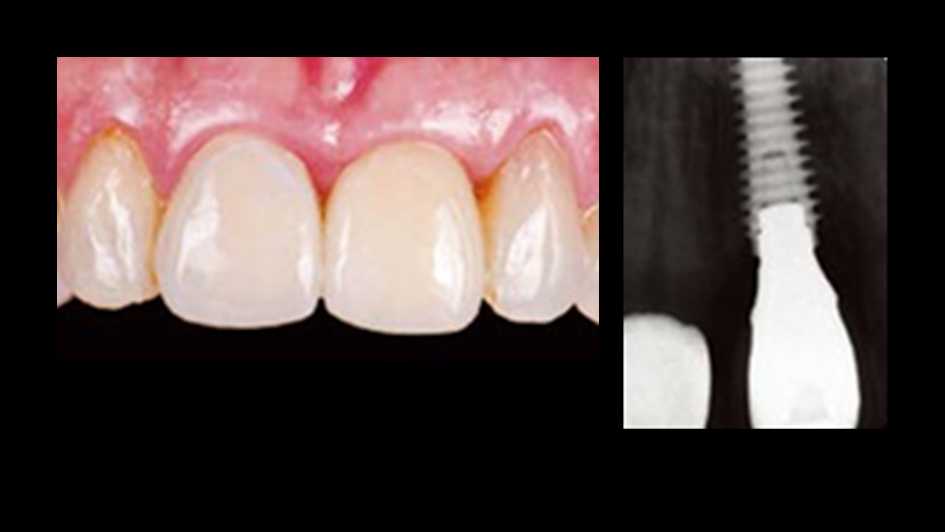

“AnyOne implant system guarantees

excellent aesthetics & functionality for any implantologist

& any patient. ”

Clinical case: Single molar implant with bone augmentation

- Courtesy of Dr. Jung Sam Lee, Korea -

Keywords

AnyOne, bone augmentation, osteotomy socket, peri-implant tissue, autogenous bone, GBR, single replacement, Auto-Max, Dr. Jung Sam Lee

Products:

AnyOne implant system, Auto-Max